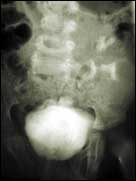

إلتهاب المثانة

يعتبر التهاب المثانة المتكرر وزيادة نسبة الخلايا الصديدية في البول من الاعراض الاكلينيكية والعملية التي تستحق الدراسة حيث ثبت علميا بان يرجع ذلك الى و.........